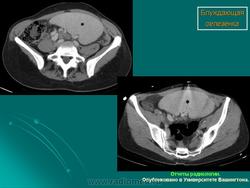

Полиспления

ID: 12761 Polysplenia syndrome , situs ambiguous, rectal mass Dr Amro Nazih Omar - 7 Jan 2011 Axial CECT demonstrates polysplenia, situs ambiguous, absent IVC an...